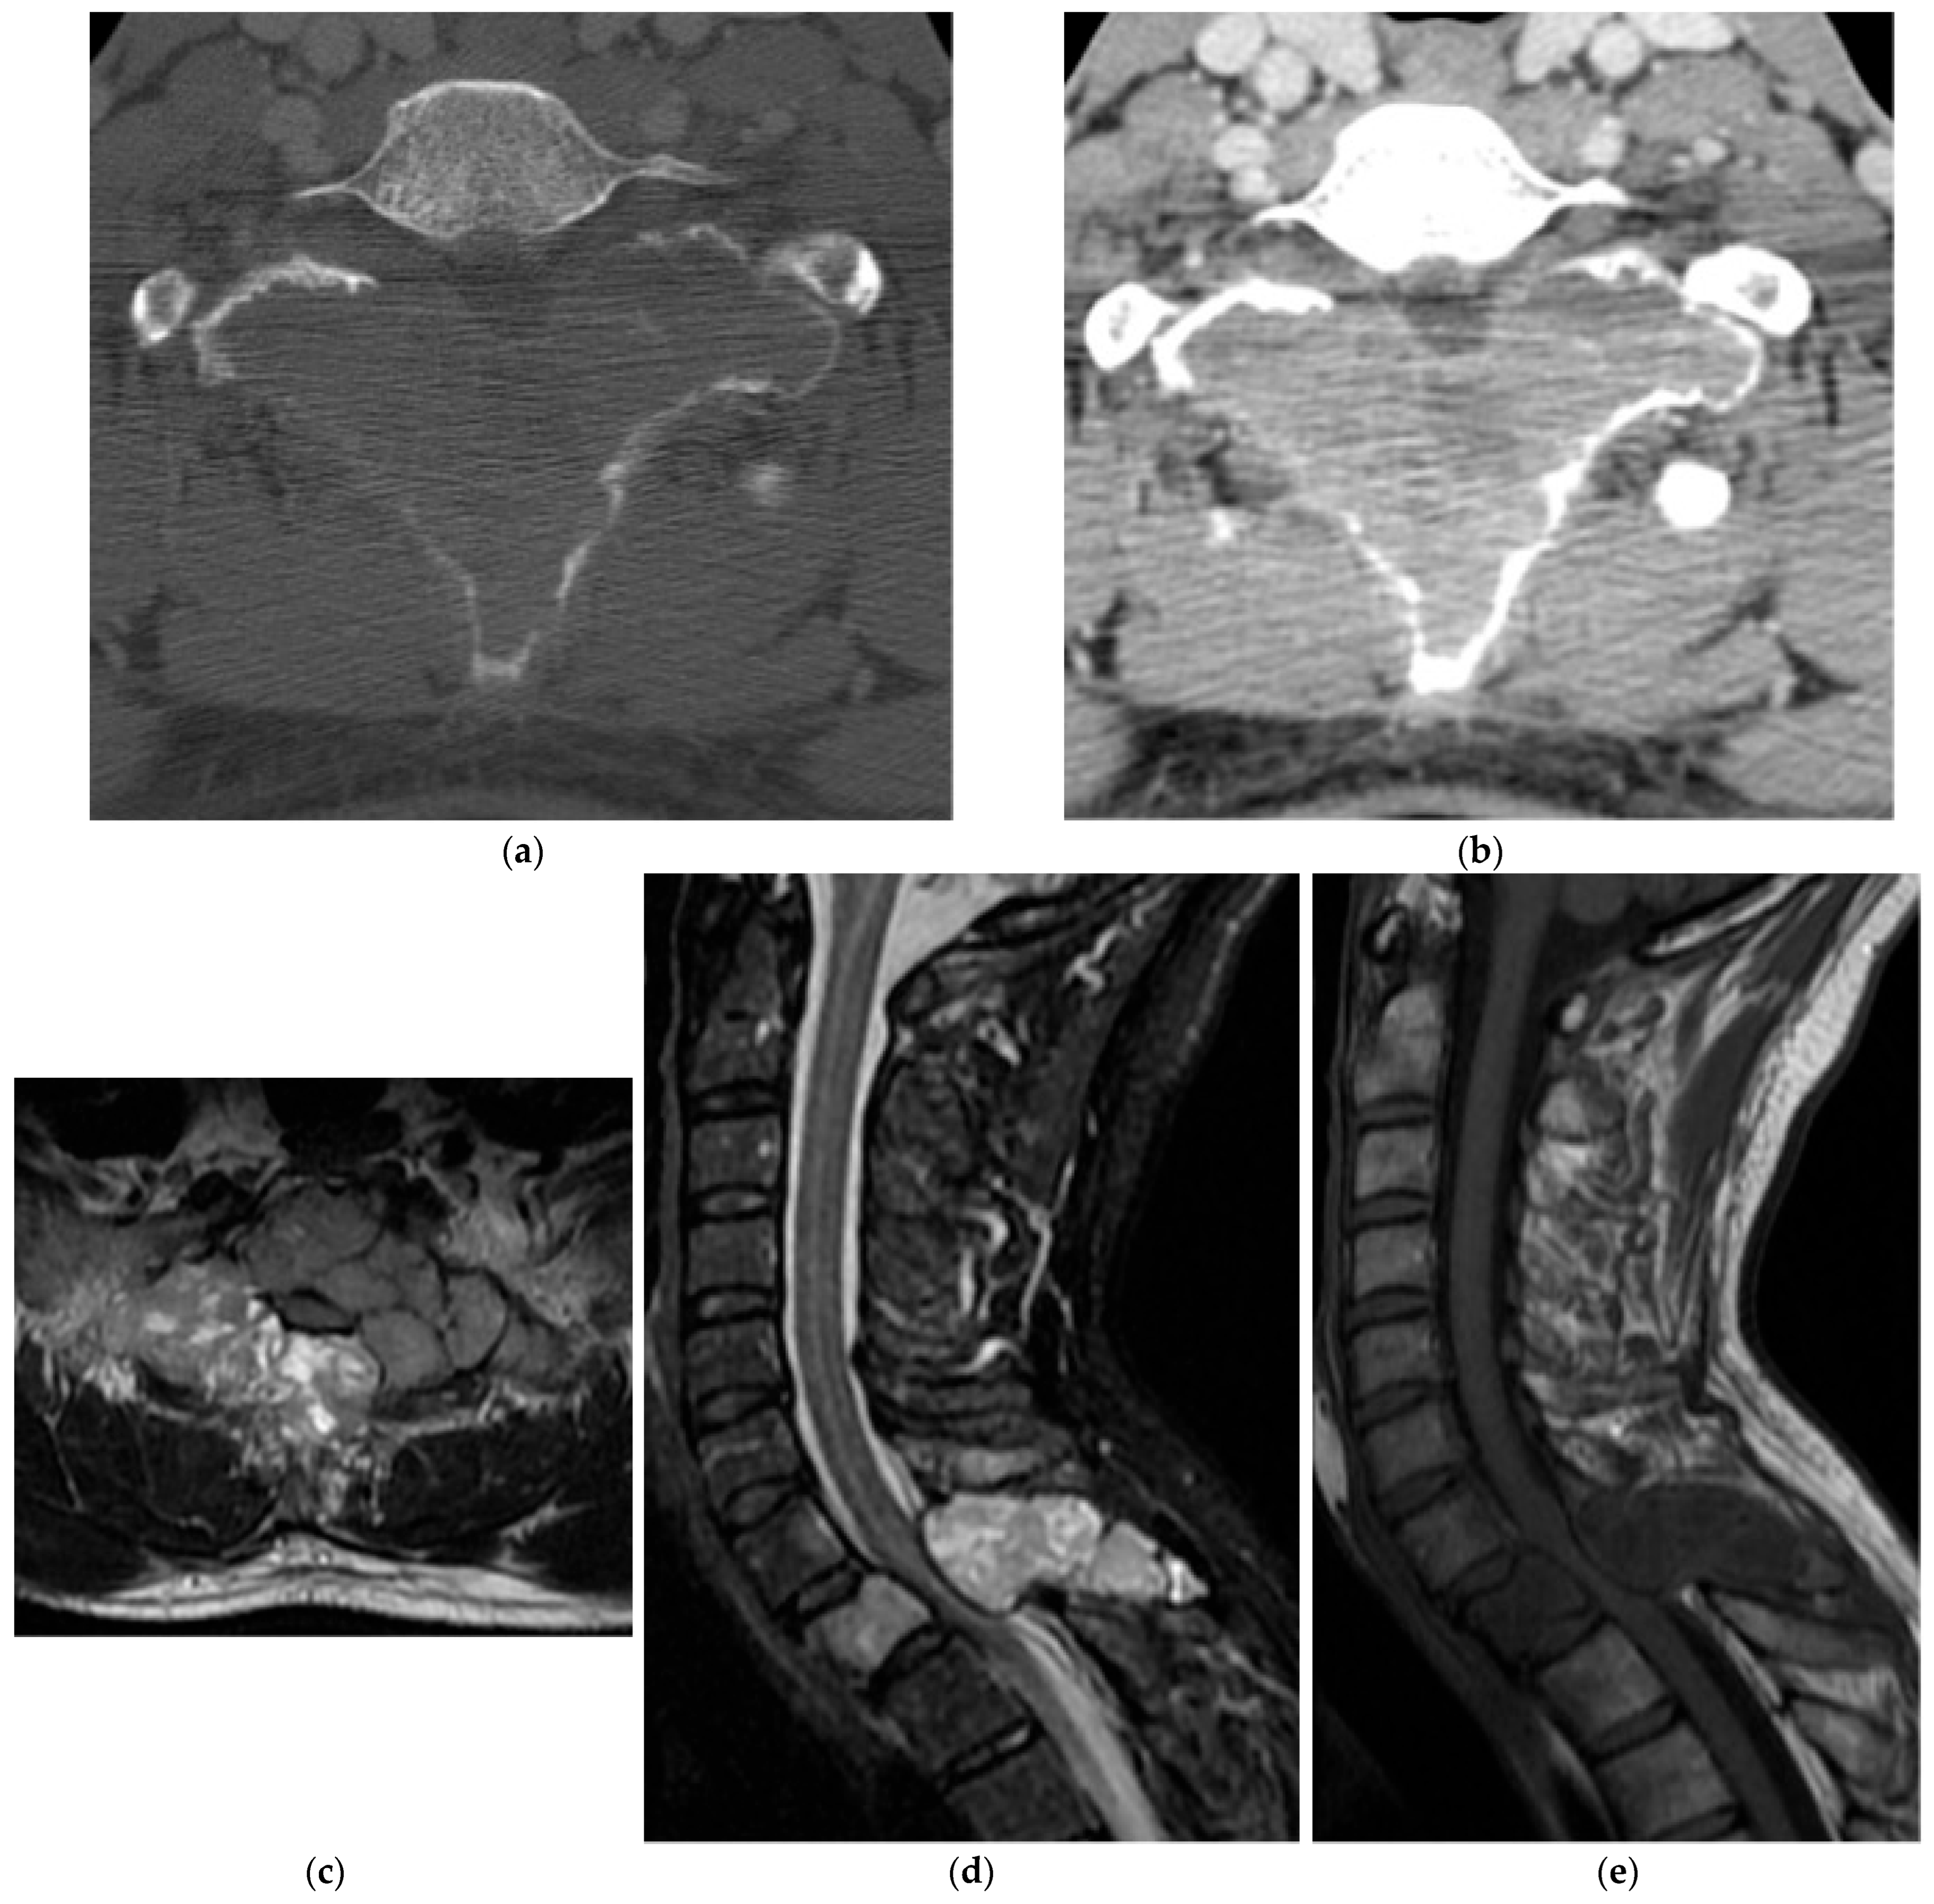

2.1.3. Osteoblastoma

2.5.2. Aneurysmal Bone Cyst